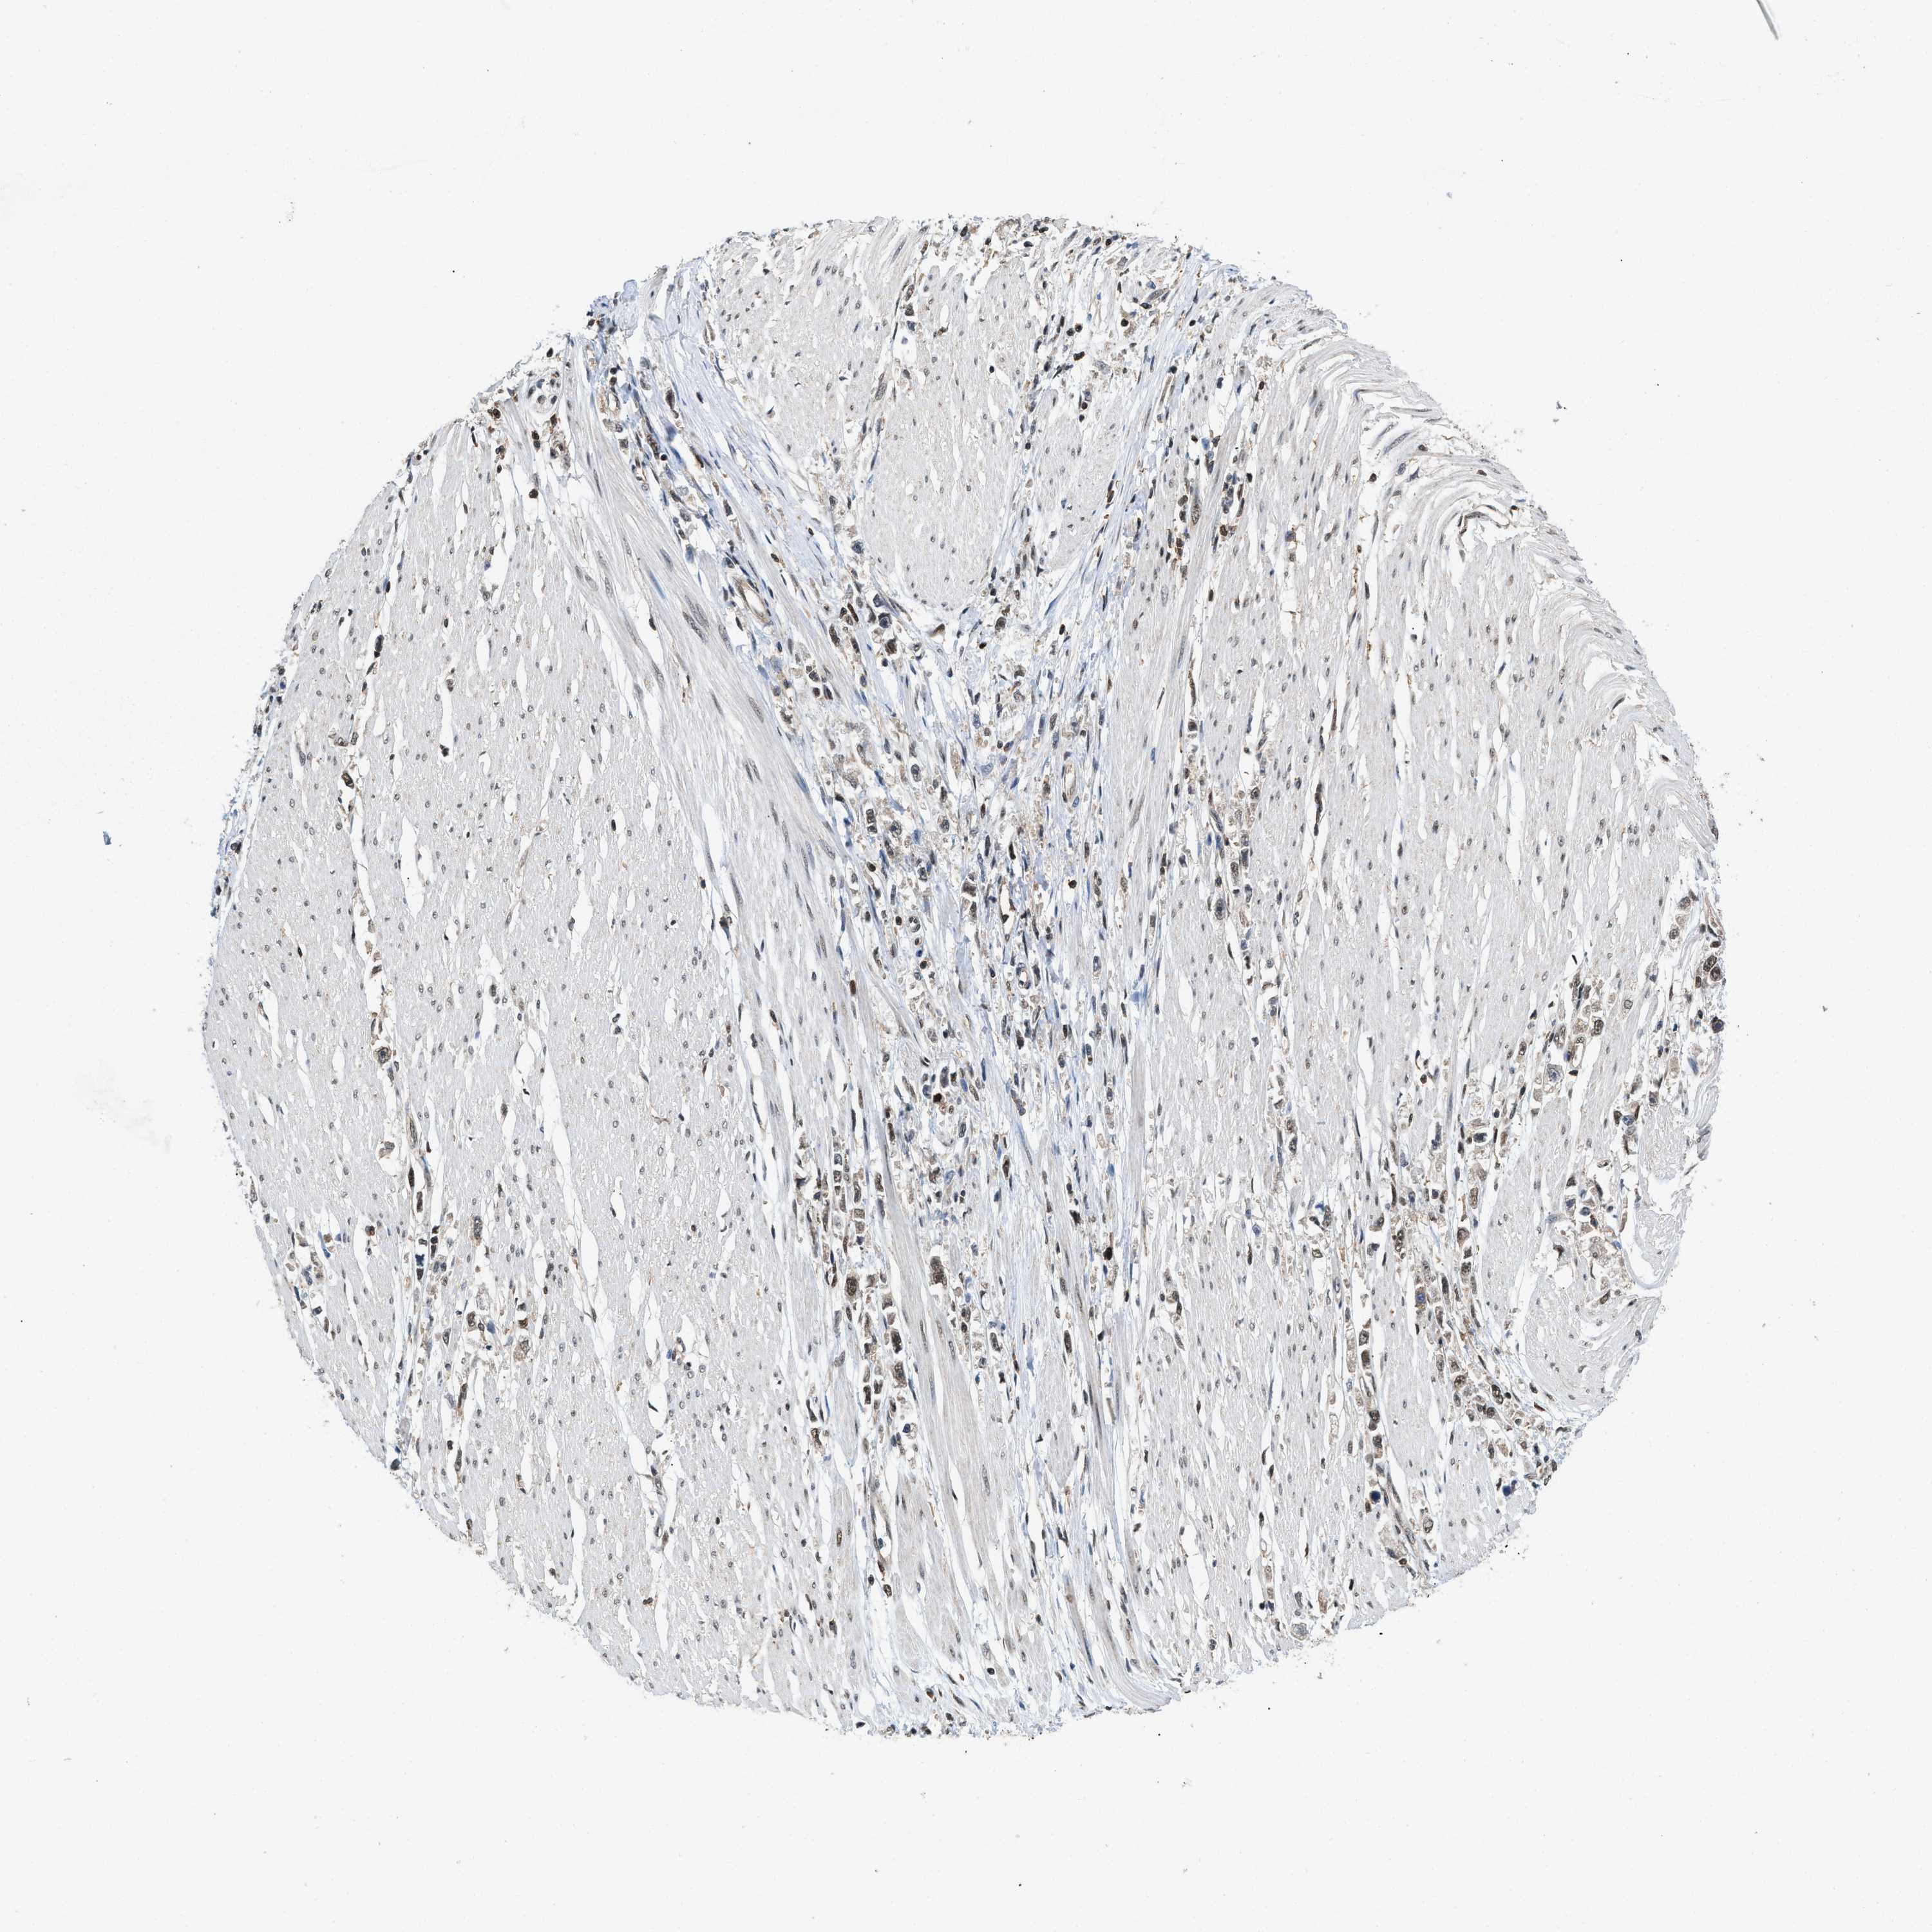

STOMACH CANCER - Protein expressioni

A mouse-over function shows sample information and annotation data. Click on an image to view it in a full screen mode. Samples can be filtered based on level of antibody staining by selecting one or several of the following categories: high, medium, low and not detected. The assay and annotation is described here.

Antibody stainingi

Antibody staining in the annotated cell types in the current human tissue is reported as not detected, low, medium, or high, based on conventional immunohistochemistry profiling in selected tissues. This score is based on the combination of the staining intensity and fraction of stained cells.

Each image is clickable and will lead to virtual microscopy that enables deeper exploration of all samples and also displays staining intensity scores, fraction scores and subcellular localization as well as patient and tissue information for each sample.

Staining

High

Medium

Low

Not detected

Intensity

Strong

Moderate

Weak

Negative

Quantity

>75%

75%-25%

<25%

None

Location

Nuclear

Cytoplasmic/membranous

Cytoplasmic/membranous,nuclear

Adenocarcinoma, NOS